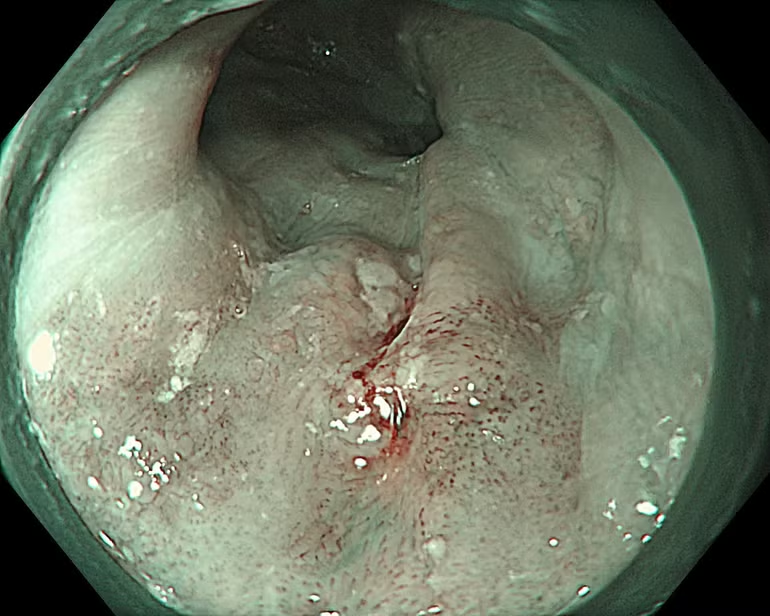

.png)

Hình ảnh thực quản tổn thương được phát hiện qua hệ thống nội soi thế hệ mới.

Các bác sĩ Bệnh viện K sử dụng hệ thống máy nội soi nhuộm màu phóng đại Olympus EVIS X1 hiện đại giúp hình ảnh sắc nét, hiển thị rõ tổn thương dù là nhỏ nhất, có chức năng nhuộm màu bằng ánh sáng và phóng đại lên đến 150 lần, giúp phân tích rõ ràng vi cấu trúc và vi mạch máu của tổn thương, đưa ra nhận định chính xác về tính chất tế bào học của tổn thương, phân biệt tổn thương ung thư và không ung thư từ đó đưa ra hướng can thiệp kịp thời cho người bệnh.

Mới đây, một bệnh nhân nam 63 tuổi, tiền sử hút thuốc lá nhiều năm khi nhập viện đã được chỉ định nội soi tiêu hóa trên trong chương trình khám sức khỏe định kỳ. Quá trình tầm soát ung thư vùng họng-thực quản được thực hiện bằng công nghệ NBI ngay từ khoang miệng, hạ họng-thanh quản đến toàn bộ thực quản. Nội soi phóng đại với hệ thống Olympus X1 và dây soi EZ1500 cho phép quan sát rõ vi mạch bề mặt đã phát hiện tổn thương gợi ý ung thư biểu mô vảy thực quản giai đoạn sớm ở lớp niêm mạc, có chỉ định điều trị bằng cắt tách dưới niêm mạc qua nội soi (ESD). Đây là phương pháp can thiệp tối thiểu, nhằm hạn chế xâm lấn, giúp tiết kiệm chi phí, đồng thời cải thiện thời gian sống và chất lượng cuộc sống của người bệnh. Sau can thiệp ESD, bệnh nhân hồi phục tốt và xuất viện sau 2 ngày.

Một bệnh nhân nam 67 tuổi, tiền sử nghiện rượu và hút thuốc lá khi sử dụng hệ thống nội soi Olympus EVIS X1 với công nghệ NBI phát hiện một tổn thương kích thước khoảng 10mm tại thực quản. Dựa trên hình ảnh nội soi và kinh nghiệm chuyên môn trong đánh giá ung thư sớm, các bác sĩ xác định tổn thương đã vượt quá chỉ định điều trị qua nội soi và được khuyến cáo phẫu thuật. Sau phẫu thuật, kết quả mô bệnh học xác định ung thư biểu mô thực quản đã xâm lấn vào lớp dưới niêm mạc, không phù hợp với các phương pháp can thiệp nội soi.